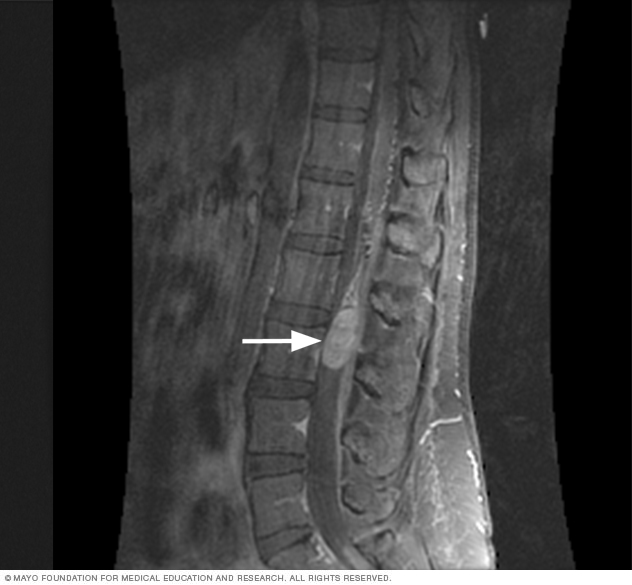

Imagen por resonancia magnética detumor de la médula espinal

Las imágenes por resonancia magnética o IRM suelen utilizarse para detectar un tumor de la médula espinal. La flecha blanca en esta imagen de resonancia magnética señala un tumor de la médula espinal.